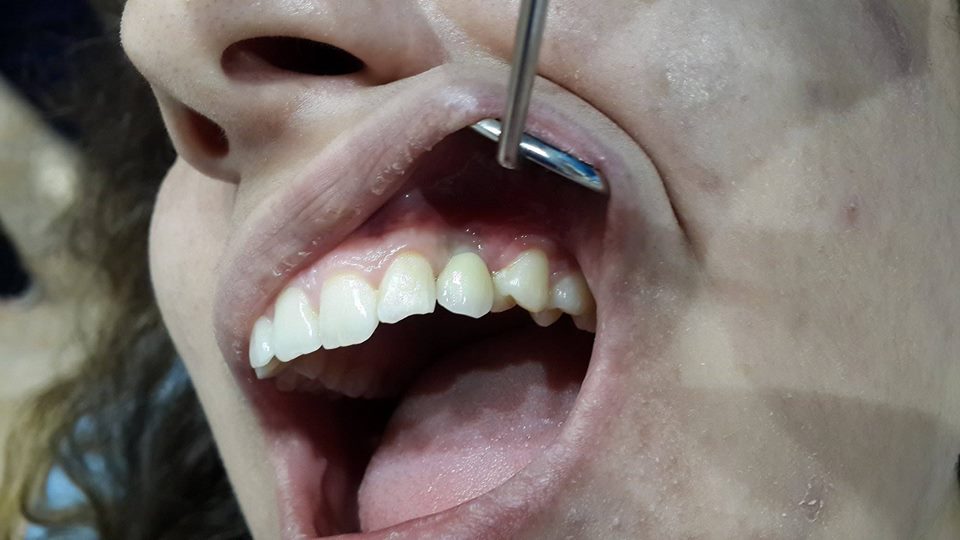

Canine restoration using implantation

To successfully restore the canine, the patient was simultaneously removed a tooth and used bone material.